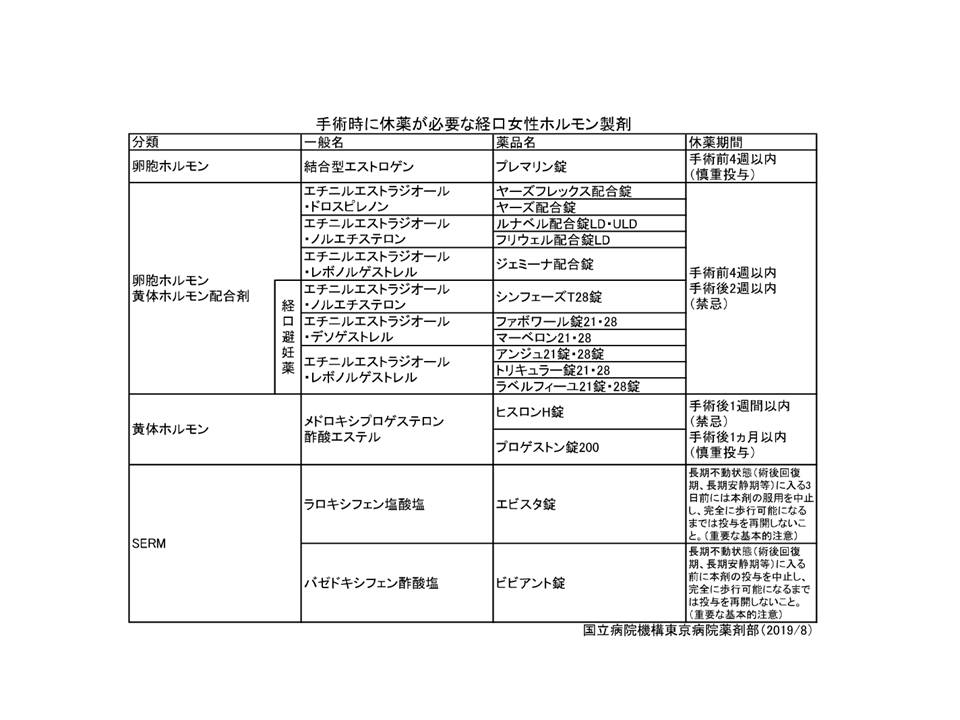

エストロゲン製剤とエストロゲン誘導体(SERM)、黄体ホルモン剤、経口避妊薬は血栓リスクがあるため、甲状腺手術前後の服薬が禁忌になっています。

- アンジュ®(レボノルゲストレル・エチニルエストラジオール合剤);甲状腺手術4週間前から術後2週まで休薬

- プレマリン®(成分:結合型エストロゲン);甲状腺手術4週間前から休薬

- バゼドキシフェン(ビビアント®);甲状腺手術前から術後完全歩行できるまで休薬

- ラロキシフェン(エビスタ®);甲状腺手術3日前から術後完全歩行できるまで休薬

- タモキシフェン(ノルバデックス®);添付文書に休薬記載は無いが、英国では休薬フローチャートが存在(Int J Surg 313-316, 2012)